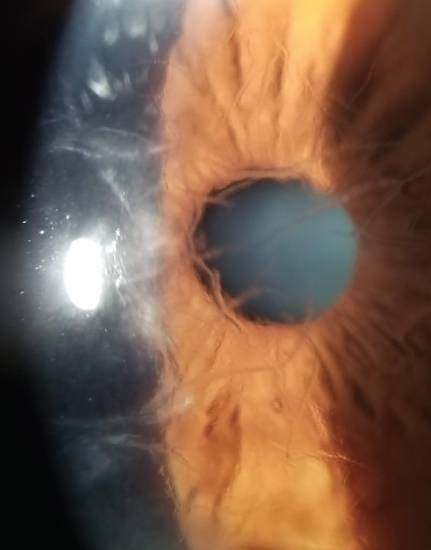

Заболевание в процессе развития проходит стадии от «cornea guttata» до субэпителиального фиброза с васкуляризацией. На стадии «cornea guttata» при биомикроскопии на уровне десцеметовой мембраны просматриваются центральные изменения в виде «битой металлической крошки» или «шагреневой кожи» с или без «напыления» пигмента. Роговичных гутт при позднем варианте дистрофии больше, чем при раннем. При уменьшении числа эндотелиальных клеток менее чем 500 в мм2 эндотелиальный слой перестает выполнять свои основные барьерные и насосные функции — развивается отек стромы и эпителия. Появляются эпителиальные пузыри — буллы (буллезная стадия), разрыв которых ведет к появлению болезненных эрозий. Субэпителиальные фиброзные рубцы и периферическая поверхностная васкуляризация могут возникнуть на поздних стадиях хронического отека. Для пациентов характерно прогрессирующее снижение остроты зрения из-за эпителиального/стромального отека. Острота зрения может быть хуже утром из-за увеличения отека. Боль, светобоязнь и слезотечение возникают из-за крупных булл и эпителиальных эрозий.